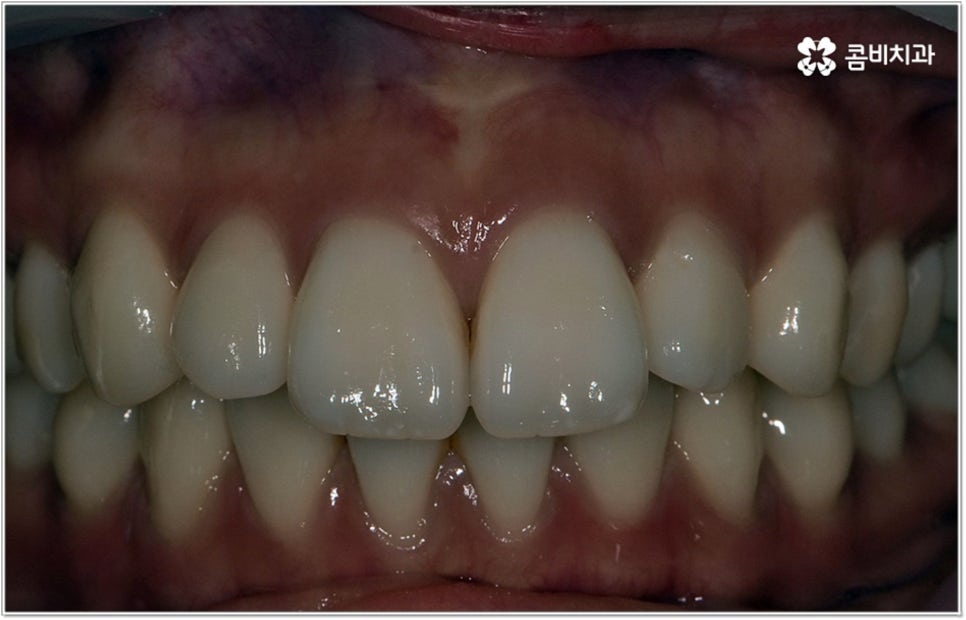

이러한 기능적인 부분 외에 심미적인 부분에서도 문제가 발생할 수 있는데요. 예를 들어 치아가 튀어나와 있다면 가만히 있어도 퉁명스러워 보이거나 화가 난 것처럼 느껴지고 입을 꼭 다물기가 어려워서 무리하게 힘을 주게 되기 때문에 입가나 턱에 주름이 질 수도 있어요. 이때 돌출입치아교정 치료를 받게 되면 위아래가 잘 맞물리는 가지런한 치열을 가지게 되는 것 뿐 아니라 자연스러운 입매와 부드럽고 균형잡힌 인상으로 바뀌게 되어 스스로 자신감 있는 태도를 가지게 되고 대인 관계에서 호감도도 높아질 거예요.